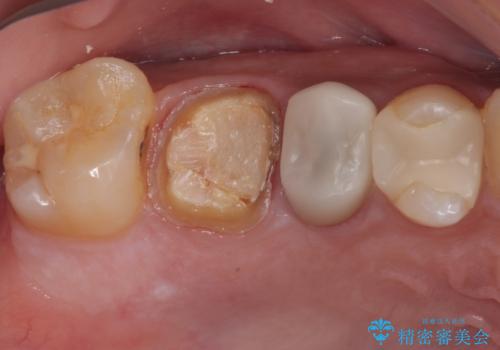

セラミックが欠けた オールセラミッククラウン

- セラミックが欠けたとのことで来院された患者様です。新しくセラミックを作り直していく治療計画としました。

拡大鏡視野下で、セラミックの被せもの、虫歯の除去を行い、オールセラミッククラウンに適した形に整えました。